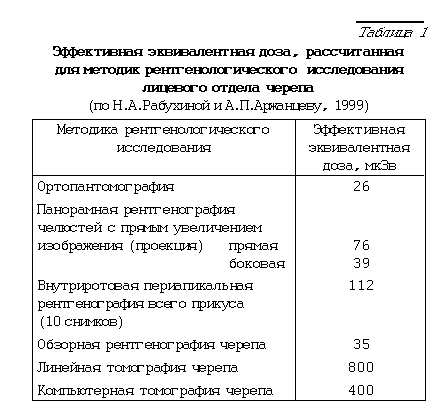

Лучевая нагрузка на пациентов оценивается посредством эффективной эквивалентной дозы (ЭЭД), которая измеряется в микрозивертах (мкЗв) и определяется путем замера облучения жизненно важных и наиболее чувствительных к воздействию ионизирующей радиации органов (хрусталик глаза, головной мозг, щитовидная железа и др.).

Как видно из приведенной таблицы, особенно велики дозовые нагрузки при исследовании всего зубного ряда, выполненного на аппарате типа 5Д-1 и 5Д-2м без дополнительной защиты. Резко снижает лучевую нагрузку на пациента исследование с помощью ортопантомографа. Дополнительное экранирование, в том числе щитовидной железы, делает исследование еще более безопасным.